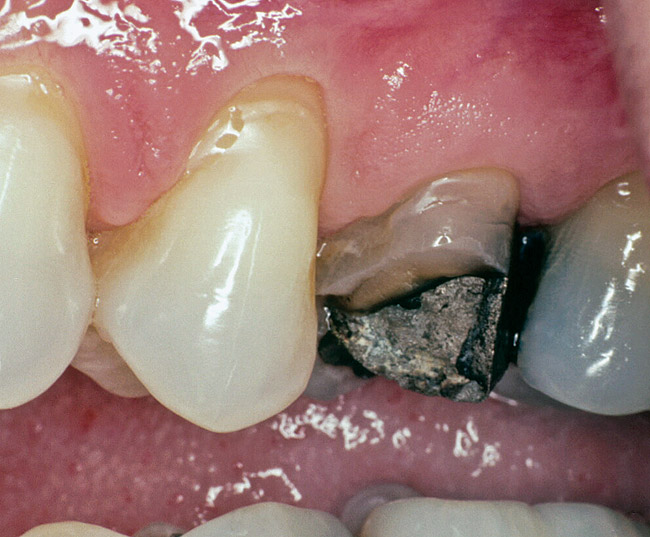

Replacement of existing restorations is responsible for 75% of all operative dentistry.15,19 The reasons for placement and replacement of restorations of direct restorative materials include: primary caries (Figure 1 and Figure 2); recurrent caries (Figure 3); poor margins (Figure 4 and Figure 5); restoration fracture (Figure 6 and Figure 7); tooth fracture (Figure 8); esthetics (Figure 9); non-carious tooth structure lost (attrition, abrasion, abfraction, erosion) (Figure 10); and pain/sensitivity.

Figure 3  Maxillary first molar with mesiobuccal tooth fracture and recurrent caries.

Figure 3